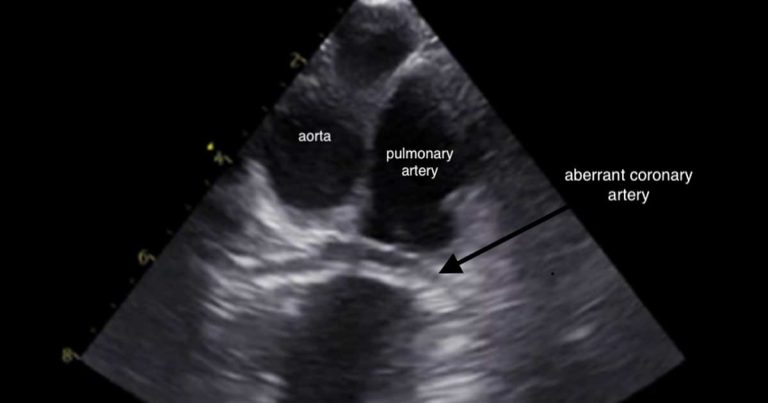

Brachycephalic breeds, particularly bulldogs, can have constriction of the pulmonary valve annulus or the subvalvular area by an aberrant coronary artery, such as with type R2A anomaly, creating a stenosis. It is important those patients with aberrant coronary arteries are identified as they are at an increased risk of rupture of the coronary artery and, therefore, fatal haemorrhage during balloon valvuloplasty.

Transoesophageal echocardiography (Figure 3), as well as CT angiography, are used in some centres to aid diagnosis.